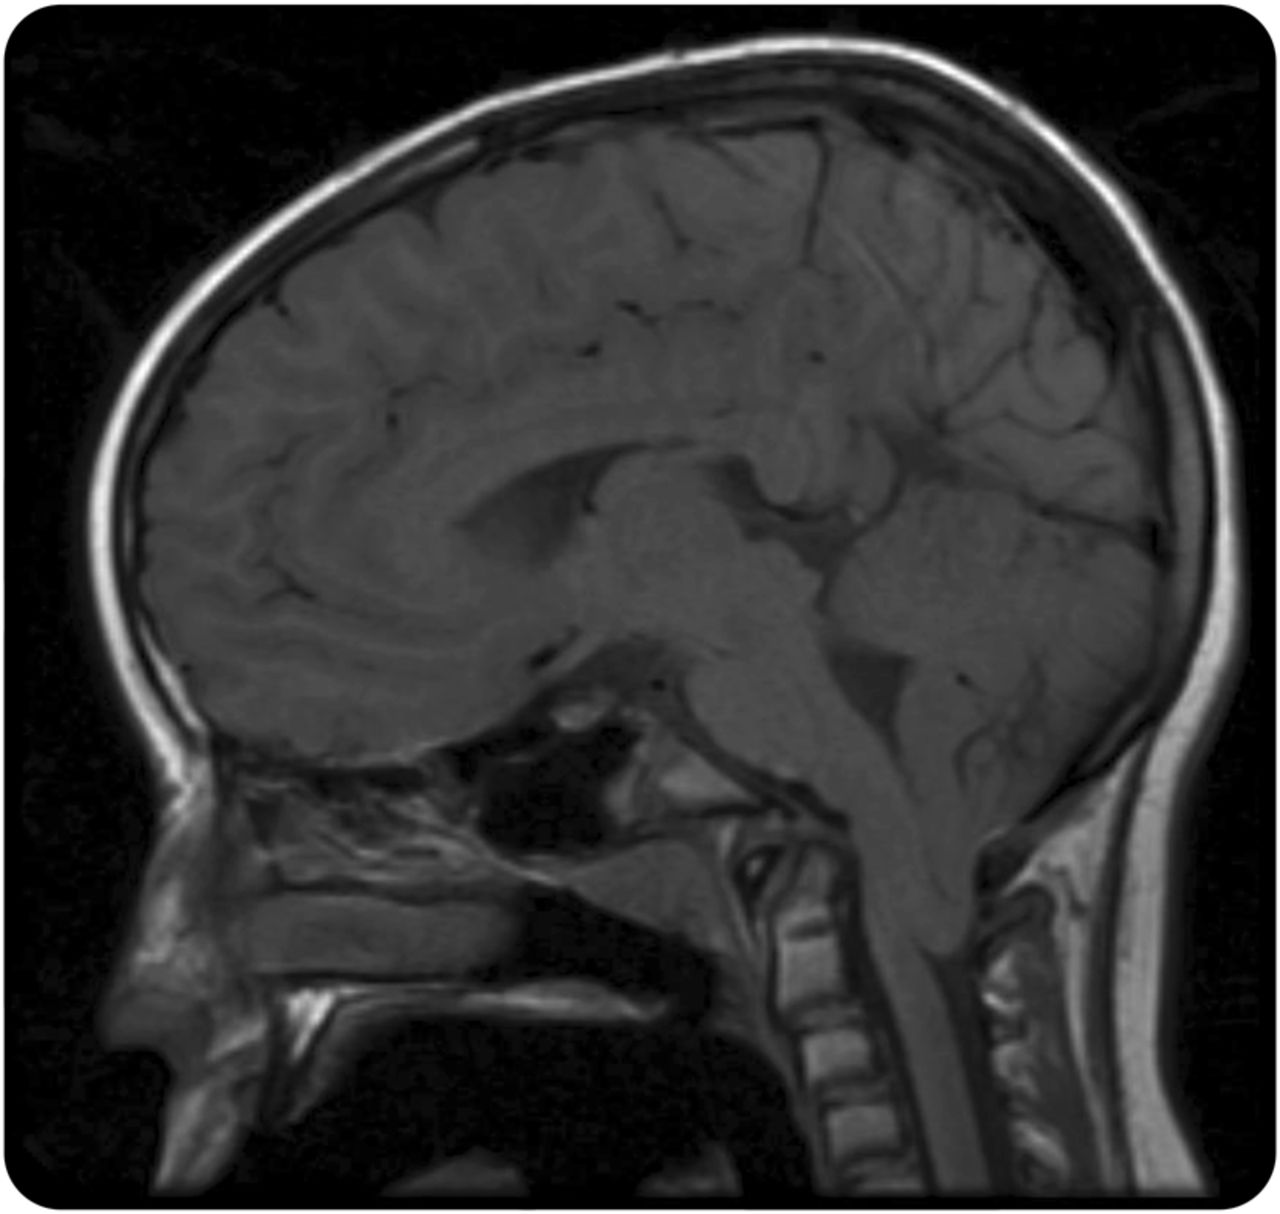

一个17岁的女孩与偏头痛和努南综合症神经咨询关于恶化头痛的设置为肺炎住院。病人报告阵发性的3年历史,衰弱,中线头痛一般持续时间不超过1分钟,增加的频率和严重程度的咨询。枕部疼痛开始的底部,然后在前面扩散到眉线。这些简短的头痛伴有咳嗽、大笑,和颈部扩展。他们在本质上是不同的从她的偏头痛,长期和畏光和呕吐。此外,病人报告最近吃饭时窒息的问题。体检是在串联步态不起眼的除了困难。大脑MRI显示20毫米扁桃体疝在枕骨大孔,拥挤的枕骨大孔,符合畸形1型(CM-I) (图)。诊断为咳嗽头痛次要CM-I。吲哚美辛开始25毫克的剂量每天两次。在随访1月后,头痛频率明显减少。